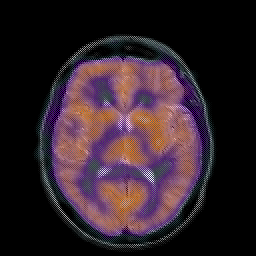

Hypertensive Encephalopathy, overlay -- Slice #13

[Home][Help][Clinical] Slice 13